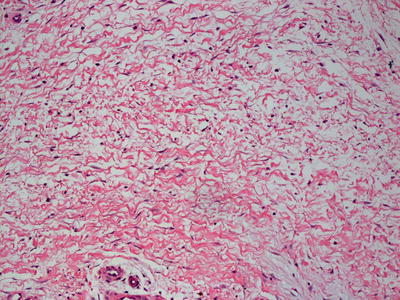

Histologic changes can be quite focal and subtle, or can be extensive [25]. In early lesions, calcium deposits may be identified solely within the walls of blood vessels. Vessels located in the deep dermis or subcutaneous fat are commonly affected (Fig. 16.4). There is little or no associated inflammatory infiltrate associated with the calcium deposits. In more extensive cases, calcium deposits also appear within the fat, unrelated to vascular deposits (Fig. 16.5) [26]. Peri-eccrine calcium deposition is a highly specific finding [27]. In severe cases, ulceration is present secondary to vascular occlusion and tissue ischemia. In these cases, a brisk and diffuse inflammatory process is observed. Interestingly, in one series, there was little evidence of internal organ calcium deposition at postmortem examination [28]. The histologic differential diagnosis includes atherosclerotic changes with secondary calcification, but this is not a frequent consideration in children.

A324456_1_En_16_Fig4_HTML.jpg

Fig. 16.4

Calciphylaxis is characterized by calcium deposits within the wall of blood vessels located in the deep dermis and subcutis

A324456_1_En_16_Fig5_HTML.jpg

Fig. 16.5

Calcium deposits are seen in subcutaneous adipose tissue away from blood vessels in some cases of calciphylaxis